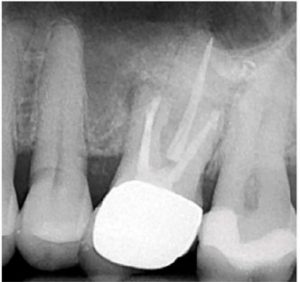

A two-dimensional intraoral radiograph revealed a prior history of root canal therapy and a porcelain-fused-to-metal (PFM) crown (both completed approximately 10years ago) (Figure 2).

After debridement and shaping, Ca(OH)2 (Ultrocal XS) was placed in the root canal space to further enhance disinfection. Prior to obturation, drainage was noted coming from the MB2 canal; drainage was arrested and the canals root was filled with vertical condensation of warm gutta percha (VCWG) and AH-Plus sealer (Figure 3)